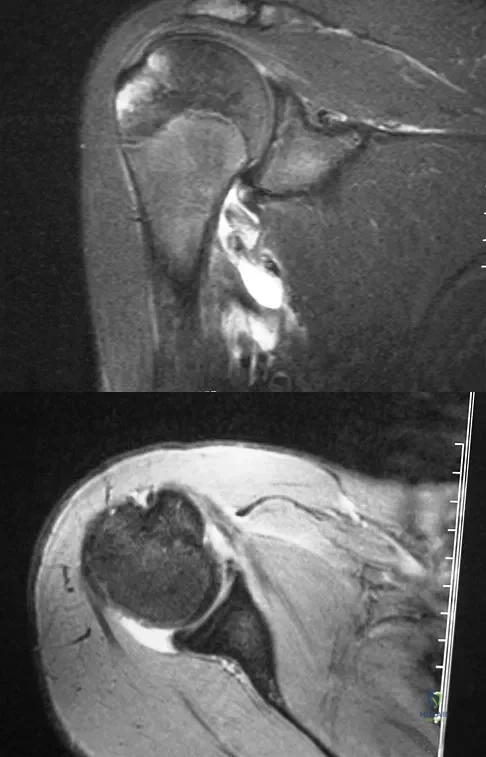

Question 39

A 45-year-old man reports right shoulder pain with overhead activities only. Figures 47a through 47d show the radiographs, bone scan, and MRI scan of a lesion of the proximal shoulder. What is the most appropriate treatment?

Explanation